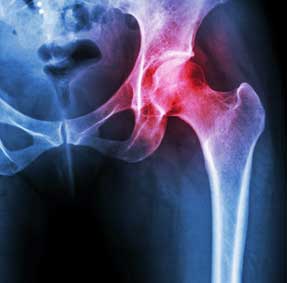

Mako is a technique used by surgeons for partial knee resurfacing, total knee replacement and total hip replacement. It is an innovative treatment option for adults living with early to mid-stage joint degeneration of the hip or knee.

After surgery, your surgeon, nurses and physical therapists will set goals with you to get you back on the move. They will closely monitor your condition and progress. Your surgeon may review a post-operative x-ray of your new joint with you.

Eligibility